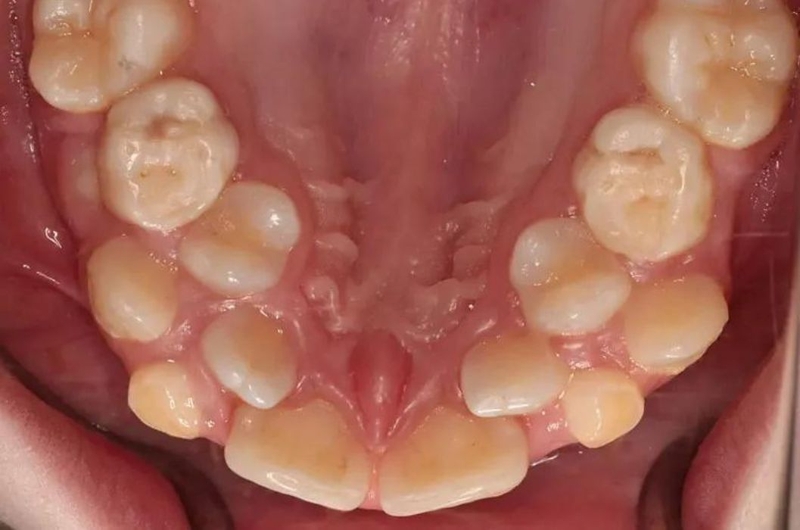

Theo thống kê, có khoảng 3,8% dân số có một hoặc nhiều hơn một chiếc răng thừa. Những chiếc răng thừa có thể mọc lên và chúng ta dễ dàng nhìn thấy. Chúng cũng có thể bị mọc ngầm nên không thể phát hiện bằng mắt thường. Hyperdontia là thuật ngữ dùng để chỉ tình trạng hàm răng của một người mọc nhiều răng hơn số lượng răng bình thường.

Thông thường, hàm răng của chúng ta khi đến tuổi trưởng thành có 32 răng, bao gồm cả 4 răng khôn. Những người chưa mọc răng khôn sẽ có 28 răng. 32 chiếc răng này được phân bổ đều trên 2 hàm răng, mỗi hàm 16 răng. Tuy nhiên, trường hợp Hyperdontia sẽ có nhiều hơn 32 răng và số lượng răng có thể không giống nhau ở từng người. Răng thừa có thể có ít hoặc nhiều và có thể mọc ở bất kỳ vị trí nào.